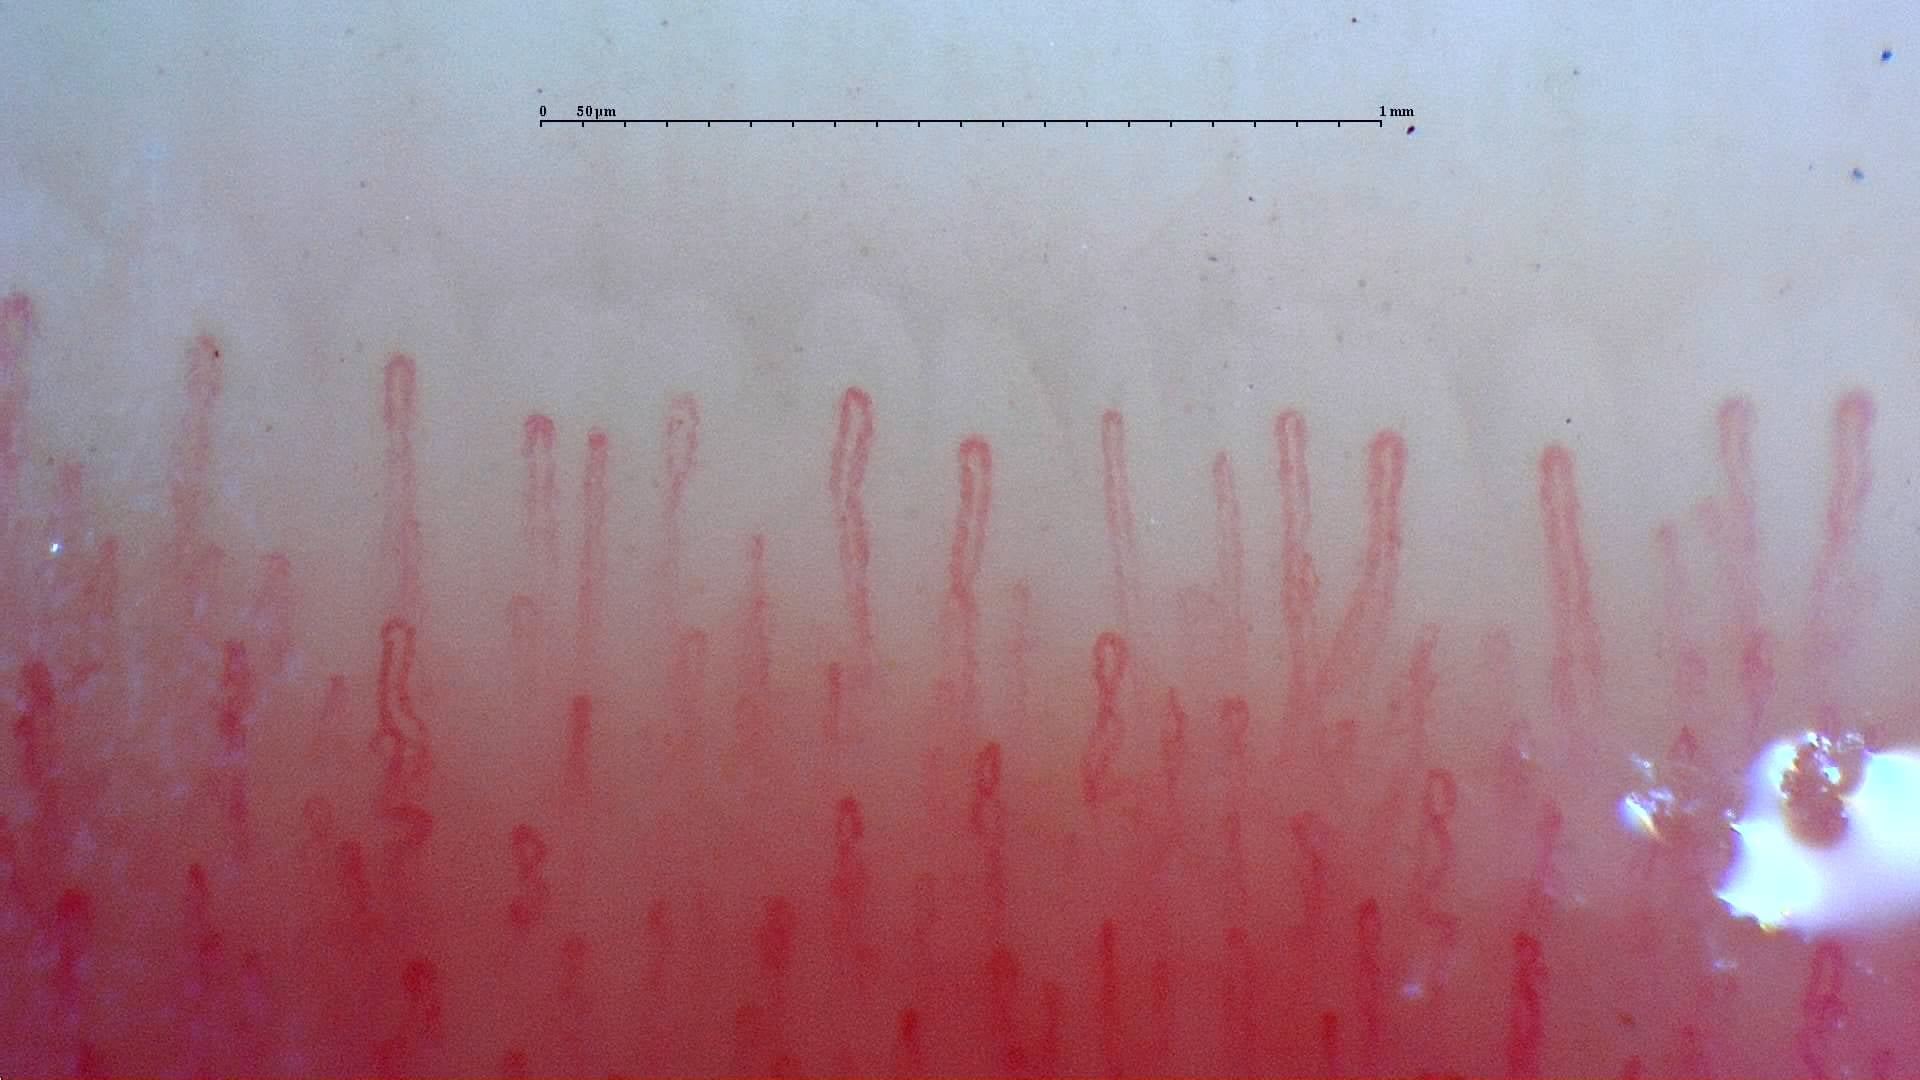

Capillaroscopy

Portable USB capillaroscopy support for nailfold capillary observation, image capture, documentation, and follow-up workflows.